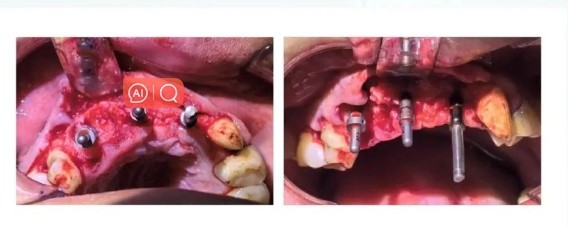

Surgical Procedure

Extraction of the affected tooth and upon flap elevation, extensive bone deficiency is observed in the mesial aspect of A4 and the distal aspect of A2.

Thorough removal of granulation tissue and positioning with a round bur.

A1B2 pilot drill positioning, and verification of axial alignment with a parallel pin.

Using a drill guide and parallel pin, gradually expanding the hole while verifying implant depth and alignment for parallelism.

Sequential implantation of three Manners Apex dental implants.